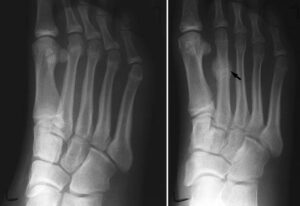

To confirm the diagnosis, doctors may order imaging tests such as:- X-rays: While initial X-rays may not detect stress fractures due to their small size, healing bone (callus) often becomes visible after a few weeks, revealing the fracture site.

(Left) This X-ray of a patient who reported pain in the second metatarsal does not show an obvious stress fracture. (Right) Three weeks later, an X-ray of the same patient shows callus formation at the site of the stress fracture.